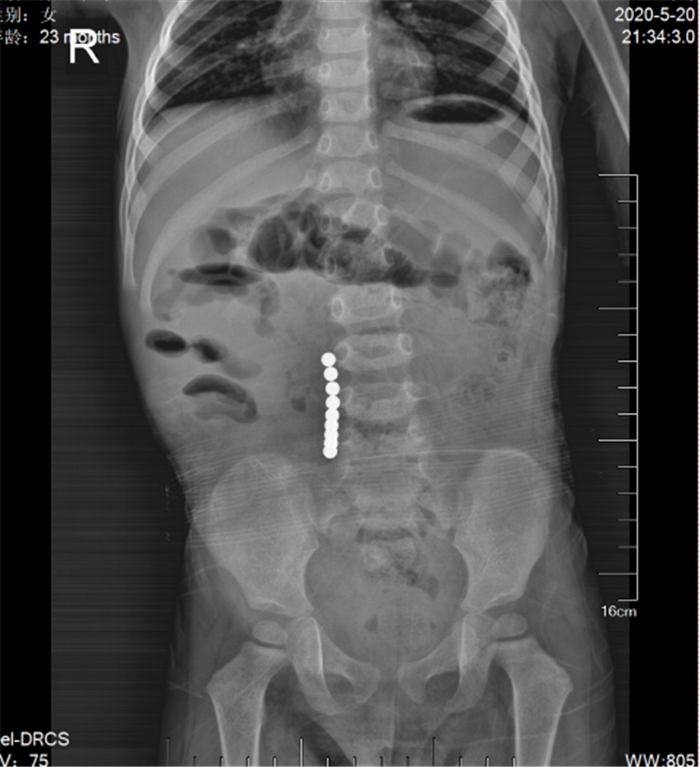

(圖2)“串珠樣高密度金屬”影像

陳博士查體發(fā)現(xiàn)患兒精神差,嗜睡,脫水貌,欠配合,腹部較膨隆,全腹輕度壓痛,無反跳痛、肌緊張,叩鼓音,上腹部尤甚,腸鳴音1次/分,陳博士考慮患兒有典型的“痛、吐、脹、閉”癥狀,“腸梗阻”可能性大,立即安排患兒做腹部臥位平片檢查,發(fā)現(xiàn)患兒右下腹有“串珠樣高密度金屬”影像(圖2),再追問患兒病史,急糊涂的父母才想起患兒3天前大便曾排出1粒玩具“磁力珠”(圖3),當時未在意。